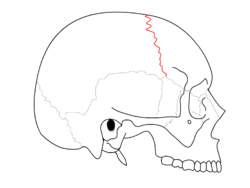

SchaedelSeitlichSutur1.png

Side view of the skull. ("Coronal suture" in red.)